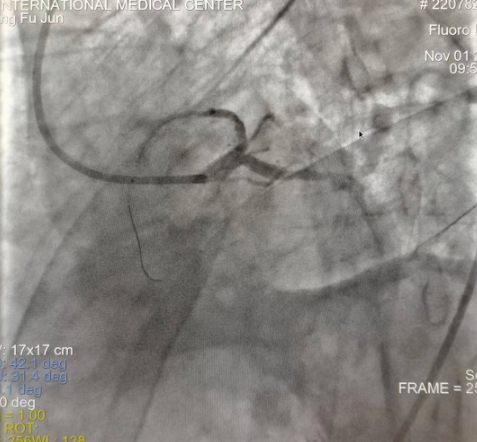

閉塞的血管再通時間取決于急救時長、轉(zhuǎn)運時長和治療時長,在前兩方面,醫(yī)院已為患者爭取了最短時間?;颊呒覍龠h在陜北,雖然已在趕來的路上,但最快抵達西安也要3小時,在與患者家屬電話溝通同意急診手術后,醫(yī)療總值班代家屬簽字,康曉軍在請示心臟病醫(yī)院王海昌院長及心臟內(nèi)科CCU尚福軍主任后,積極進行術前準備。在沒有家屬陪同、沒有交費、沒有辦入院手續(xù)的情況下,患者經(jīng)胸痛中心綠色通道被送往心臟冠脈介入手術室,打通了完全閉塞的心臟前降支近段血管。